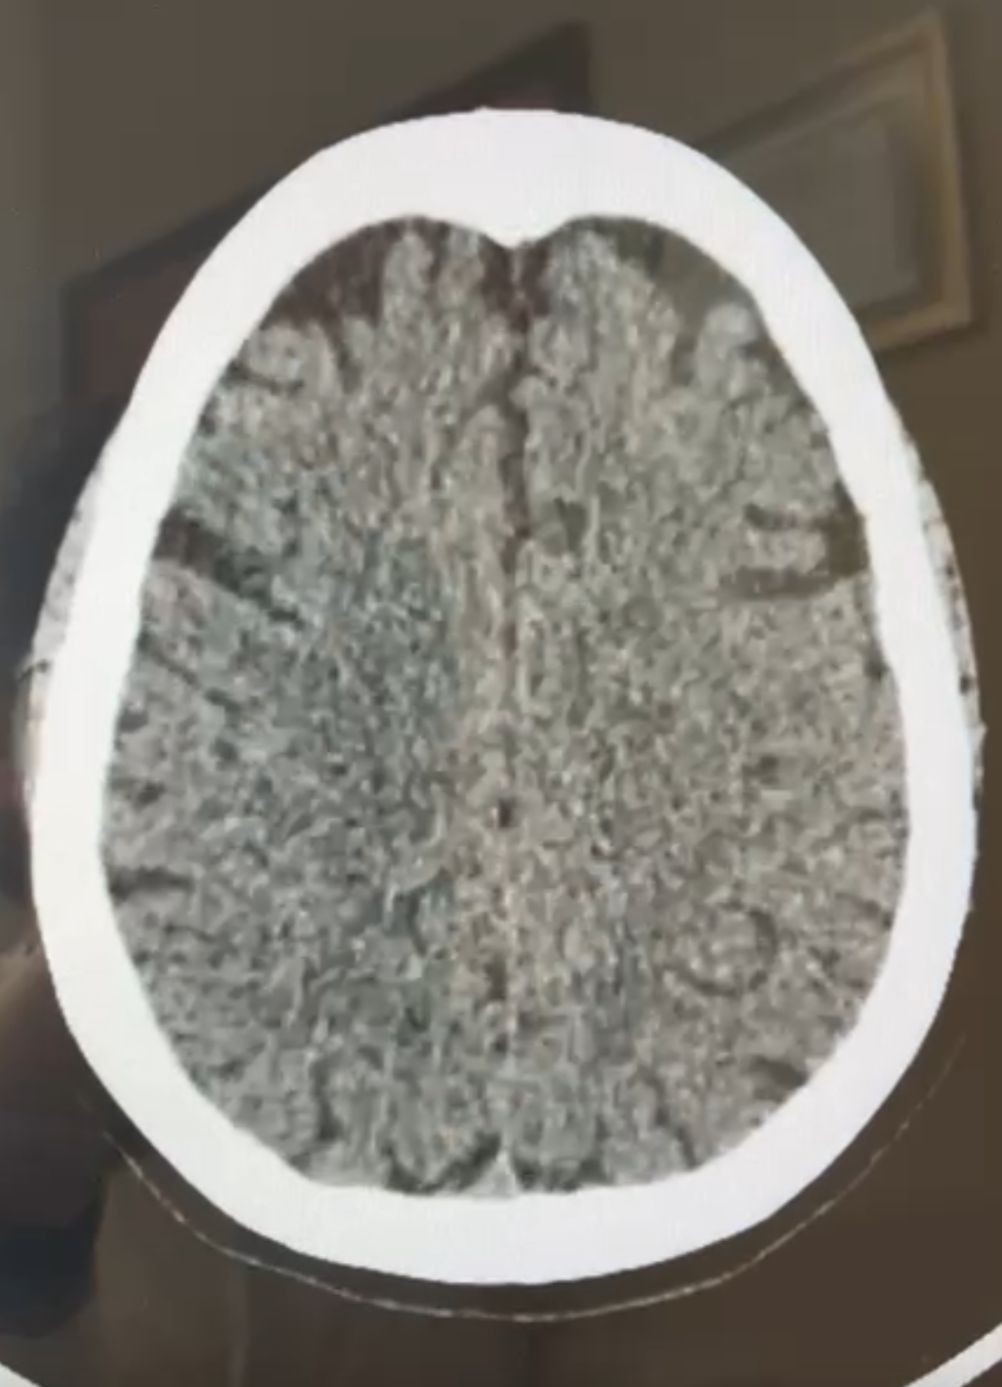

Derechohabiente de Pensiones Civiles recupera movilidad y habla gracias a cirugía de rescate cerebral vascular

_- El procedimiento fue realizado a una mujer de 72 años de edad por el médico especialista Alejandro Rodríguez Orozco, con el equipo de...